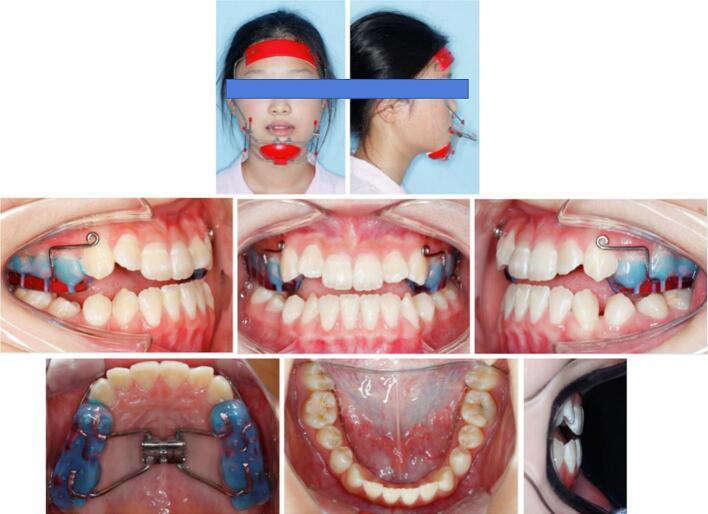

This case report describes the camouflage treatment of a severe skeletal Class III adolescent at the post-pubertal stage.

Protraction facemask combined with a bonded acrylic splint expander was initially used to correct the developing skeletal Class III malocclusion. Then the patient received fixed appliance therapy. The duration of active treatment was 14 months. Anterior crossbite was corrected, along with stable occlusion and harmonious facial condition. The results remain stable at the 5-year follow-up period.